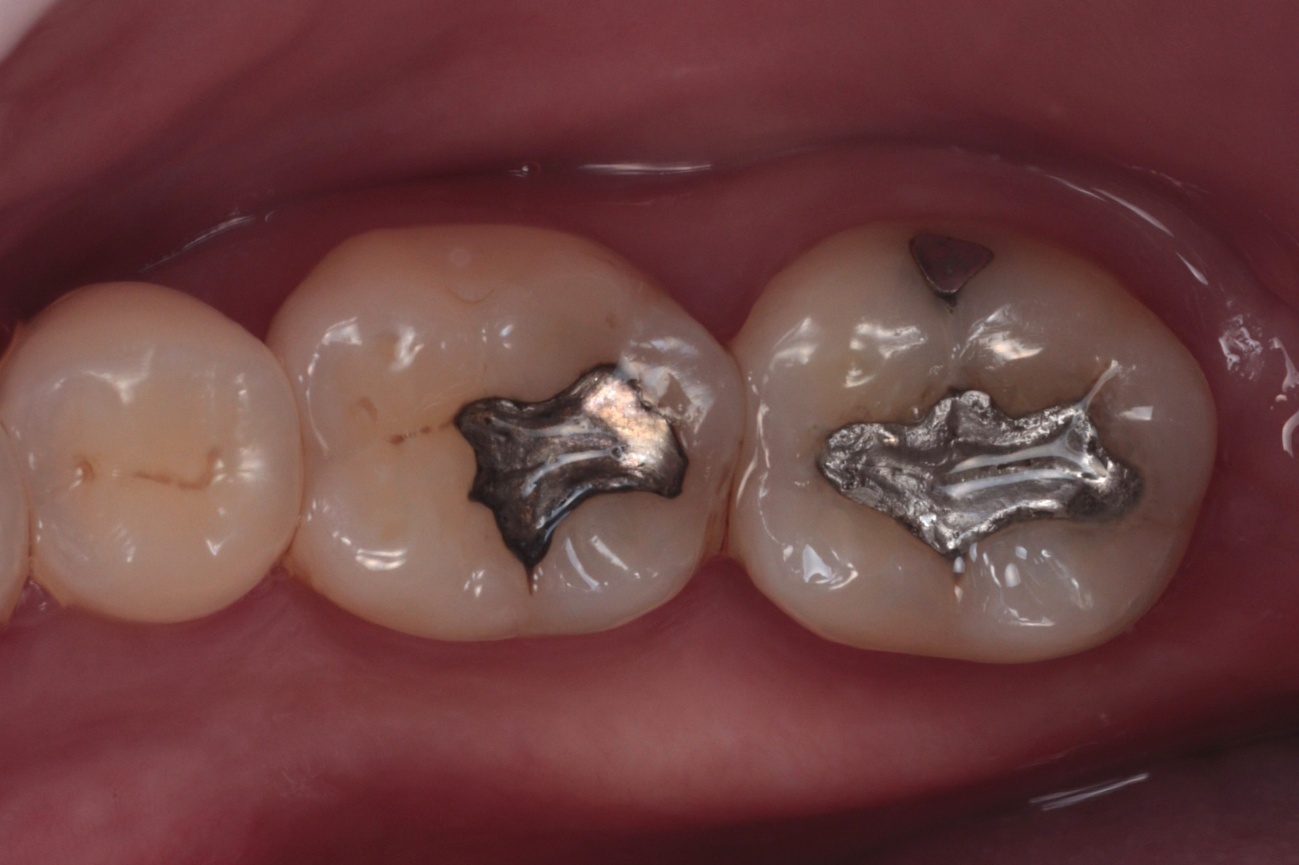

Paciente do sexo feminino, 42 anos, relatou insatisfação com a aparência escurecida de restaurações antigas em amálgama nos dentes 46 e 47. Ao exame clínico, observou-se restaurações metálicas extensas nos dentes posteriores inferiores direitos, sendo classe I no dente 46 e classe V associada à face oclusal no dente 47 (Figura 1).

Figura 1 – Fotografia inicial